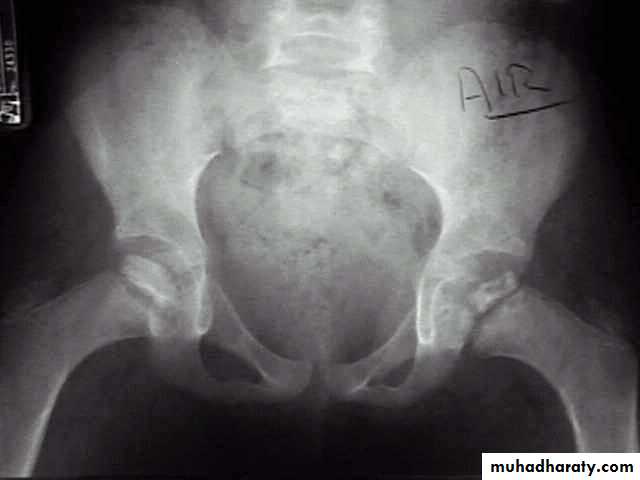

X-ray

1- at the beginning the x- ray look normal some time we can see asymmetry of the ossific centers ; bone scan is helpful at this stage (showing the avascular area) .

2- later on the increase density of the ossific nucleus will be clear ; and there is increase in the joint space .

3- fragmentation of the epiphysis .

4- flattening and lateral displacement of the epiphysis .5- widening of the metaphysis .

6- in sever and advance cases the head become mushroom shape .